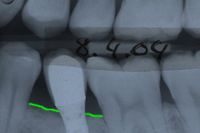

Bei einer 59 Jahre alten Frau muss wegen Wurzelbruchs und Vereiterung des ersten Brückenpfeilers (1. Zahn im Röntgenbild von Abb. 1 links) ein Zahn gezogen und das folgende Zwischenglied der Brücke rechts davon (schwarze Pfeile in Abb. 1) entfernt werden. Es entsteht im Oberkiefer links eine unschöne, ästhetisch sehr empfindliche Lücke von 14 mm.

In Abb. 2 sieht man, wie wir einen Sinuslift gemacht haben, um zwei Implantate setzen zu können. Dabei verwendeten wir ein Transplantationsgemisch mit 10% Eigenknochen und 90% Substitut. Der ortsständige Knochen beträgt beim ersten Implantat 12 mm (nur die Implantatspitze hätte in den ehemaligen Sinus geragt), beim zweiten Implantat 6 mm.

| Verlauf des Kieferhöhlenbodens vor Sinuslift | |

| Verlauf des Kieferkammes | |

| Gebiet zwischen gelber und grüner Linie: ortsständige Knochenhöhe | |

| Neuer Verlauf des Kieferhöhlenbodens | |

| Gebiet zwischen roter und grüner Linie: Knochenaufbau, Sinuslift | |

In Abb. 3 sind die zementierten Implantatkronen sieben Monate nach dem Sinuslift im Röntgenbild zu sehen. Die eigenen, bestehenden Kronen hinter den neuen Implantatkronen konnten somit gerettet werden. Abb. 4 zeigt das klinische, intraorale Resultat zwei Jahre nach der Behandlung und Abb. 5 das "happy smiling" der extraoralen Situation nach der Behandlung.